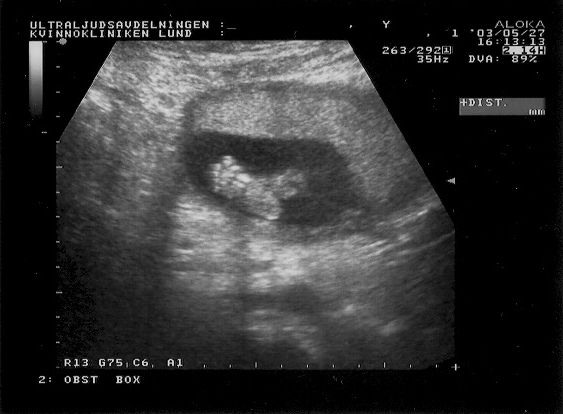

Ultra sound images from May 27, 2003.

The fetus is here 20cm tall and approx 20 weeks old.